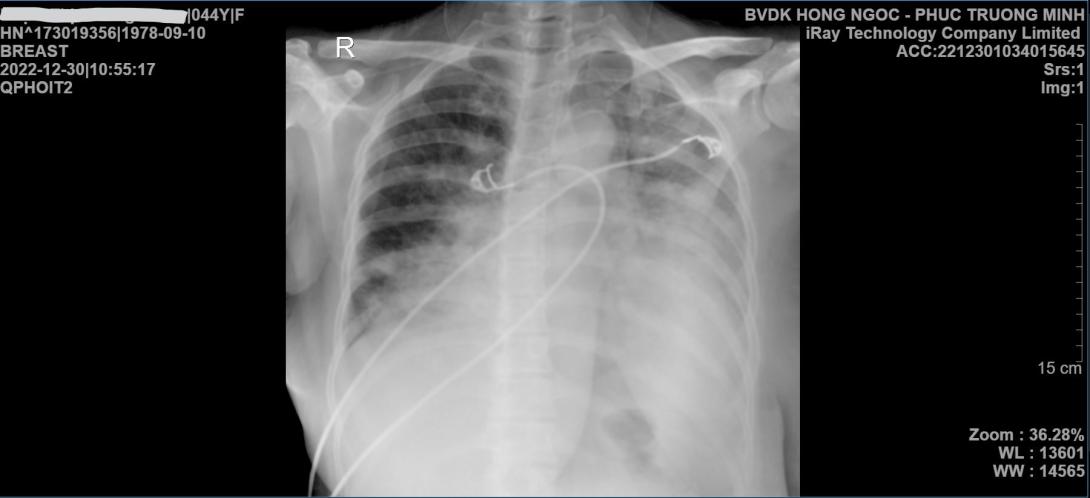

Hội chứng suy hô hấp cấp tiến triển (ARDS) là biến chứng nặng nhất của các chủng cúm nguy hiểm (như H5N1, H1N1). Tình trạng này khiến phổi bị tổn thương nặng nề, phù nề và không thể thực hiện chức năng trao đổi oxy, dẫn đến suy đa tạng nhanh chóng nếu không được xử trí bằng các kỹ thuật hồi sức chuyên sâu.

• Thông khí nhân tạo (Thở máy) chiến thuật bảo vệ phổi: Sử dụng thể tích lưu thông thấp để tránh gây áp lực quá mức lên nhu mô phổi đang bị tổn thương.

• Huy động phế nang: Áp dụng các kỹ thuật như PEEP (áp lực dương cuối kỳ thở ra) liều cao hoặc Tư thế nằm sấp (Prone Positioning) để cải thiện sự phân bố oxy trong phổi.

• Hỗ trợ cơ học ngoài cơ thể (ECMO): Trong các trường hợp thở máy không còn hiệu quả, hệ thống tim phổi nhân tạo (ECMO) sẽ được kích hoạt để thay thế chức năng phổi, giúp phổi có thời gian nghỉ ngơi và hồi phục.